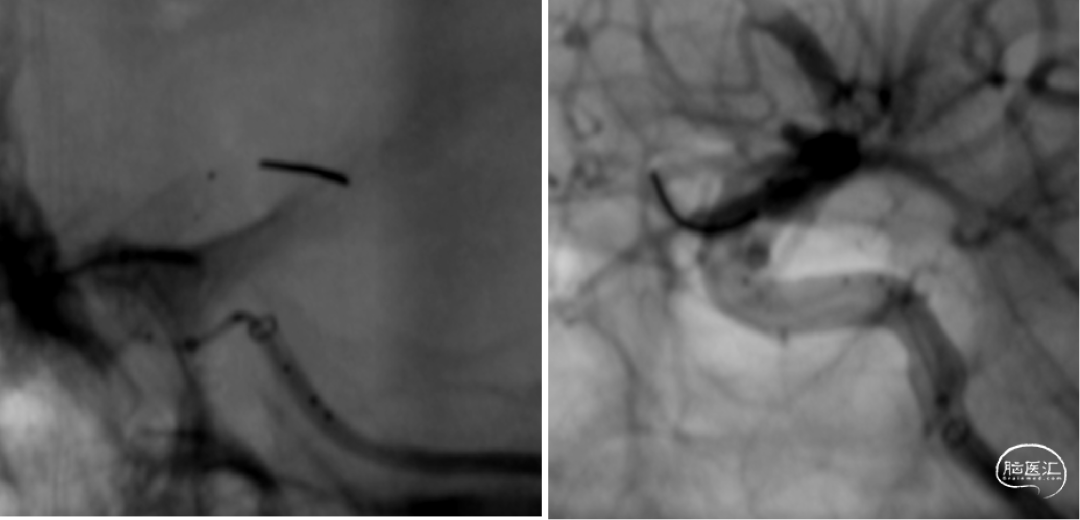

通桥微导丝导引支架管到位

支架鞘置入Y阀高压快速水化

支架释放过程(4倍速),重点是过弯推拉。

支架精显